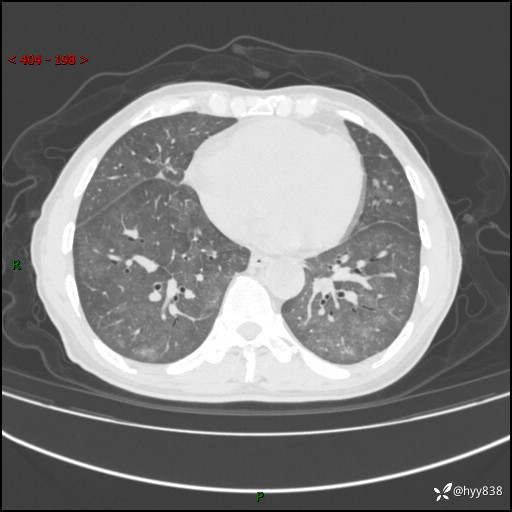

肺结节入院,CT却发现肺部弥漫性病变,what happened---(有结果)

主诉:检查发现左上肺结节4天

简要病史:患者于2024-01-15当地市人民医院胸部CT提示:左肺上叶(69)结节,最大截面约1.0 x 1.2cm,肿瘤病变待排。现患者活动后呼吸困难,自述平地行走200m后胸闷气喘,不伴咳嗽咳痰、头晕、恶心、呕吐等不适,未行特殊处理。现患者为求进一步治疗,于我院就诊,门诊拟“左上肺结节”收入院。 自患病以来患者食欲差,精神、睡眠尚可,大小便正常,体重近1月来下降5kg左右,体力明显减轻。

辅助检查:CT

胸部CT平扫

不是讨论肺部结节